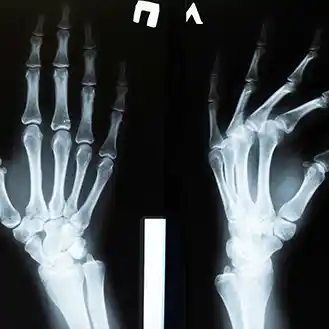

- 엑스레이(X-ray)나 초음파 검사를 통해 정확한 원인을 파악할 수 있습니다.